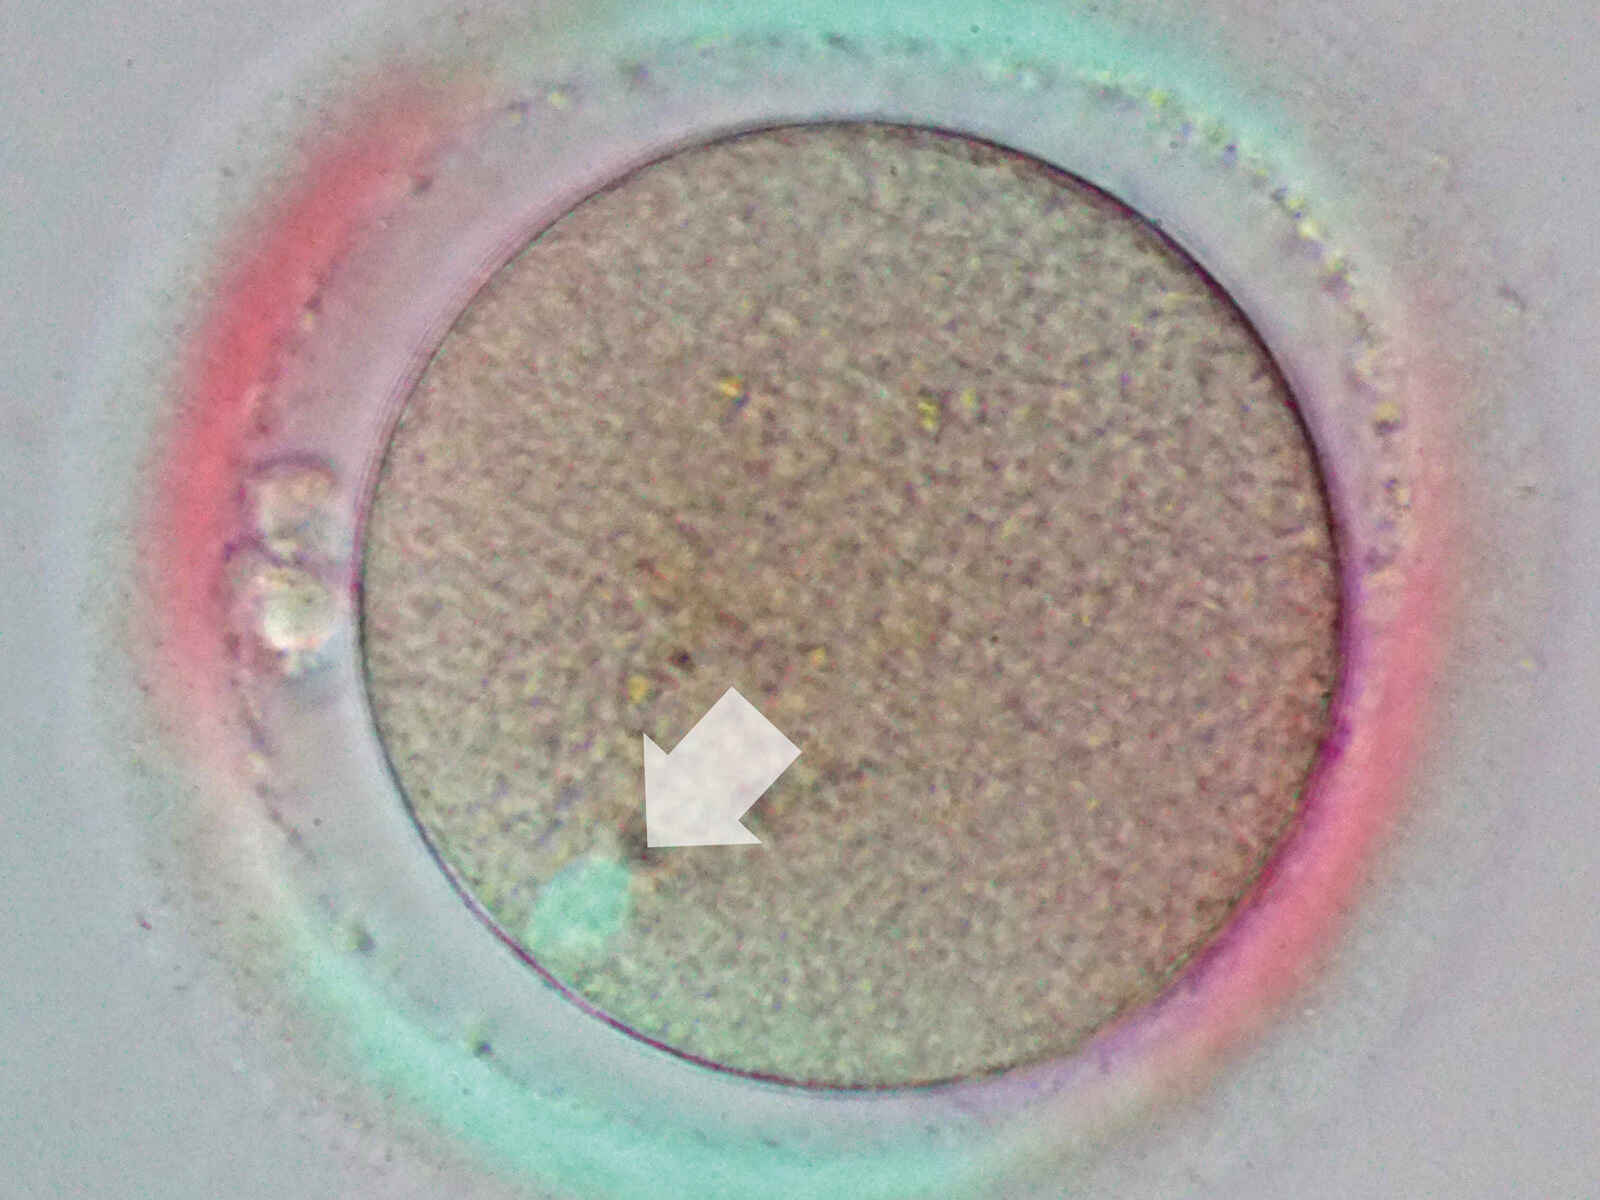

Die NAMC-Technik von Nikon (Advanced Modulation Contrast) ermöglicht die kontrastreiche Betrachtung von farblosen und transparenten Proben durch Plastikschalen. Der NAMC erzeugt einen reliefartigen Schattierungseffekt, ideal für ICSI. Durch Drehen des Modulators in einem NAMC-Objektiv kann die Schattierungsrichtung um 360 Grad angepasst werden.

In der Injektionspipette ist deutlich eine Spermazelle zu erkennen.

Bilder mit freundlicher Genehmigung von: Derek Keating, B.A. and Gianpiero D. Palermo, MD, PhD., Andrology and Assisted Fertilization: Weill Cornell Medicine - Ronald O. Perelman and Claudia Cohen Center for Reproductive Medicine.

Diese Polarisationslichttechnik ermöglicht eine fein detaillierte Betrachtung von Spindelkörpern für die Eizellenbeurteilung und die Vermeidung von Spindelschäden während der Spermieninjektion.